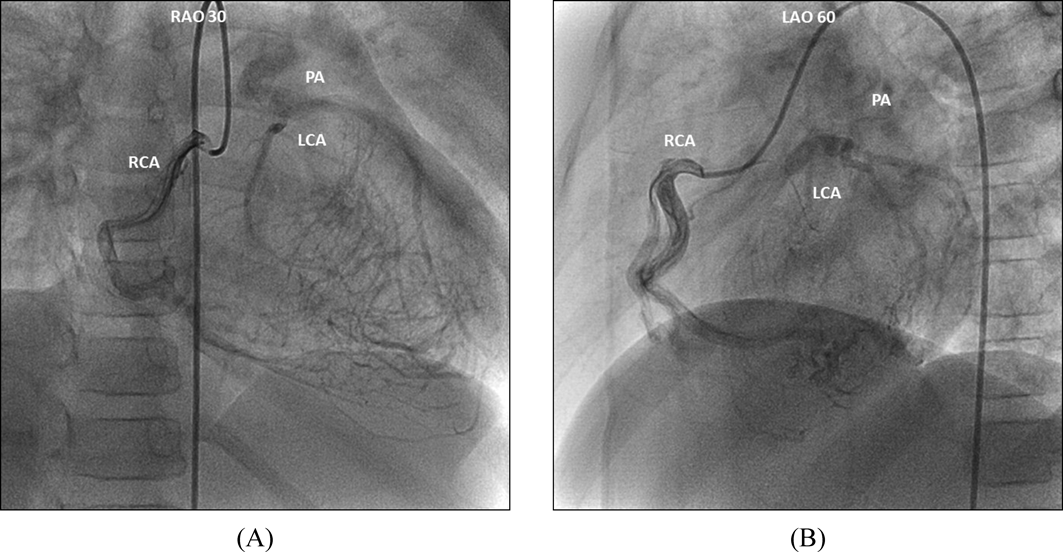

Coronary X-ray computed tomography showed the left coronary artery originated from the pulmonary artery indicating the diagnosis of ALCAPA. Cardiac catheterization and coronary angiography (Fig. 3) of the right coronary artery showed peripheral collateral vessels connecting the left coronary artery; thereby, confirming the presence of retrograde blood flow in the left coronary artery. Mild hypokinesia was observed in the anterolateral wall of the left ventricle. Further, the left ventricular end-diastolic volume was mildly increased to 138% of the normal and the left ventricular ejection fraction was 68%. Adenosine stress myocardial perfusion scintigraphy showed widespread perfusion defect in the anterior to anterolateral walls of the left ventricular myocardium during stress with no reperfusion in some regions, mainly in those supplied by the diagonal branches of left anterior descending artery. Although the patient had limited symptoms, some regions of the myocardium had already lost viability. After 2 months the patient underwent surgical correction to prevent the sudden death. The orifice of the left coronary artery was located very close to the aorta in the middle of the left facing cusp of the pulmonary artery. The left coronary artery was dissected and grafted directly into the aorta. The postoperative course was uneventful, and coronary angiography performed 2 months after the surgery showed smooth blood flow from the aorta to the left coronary artery without stenosis. The patient currently receives outpatient care at our department.

Journal of Pediatric Cardiology and Cardiac Surgery 7(1): 36-40 (2023)

Fig. 3 Selective right coronary angiography

Selective right coronary artery angiography illustrates reverse blood flow from the right coronary artery through multiple collateral vessels and subsequent draining of the blood from the left coronary artery into the main pulmonary artery. LAO, right anterior oblique view; LCA, left coronary artery; PA, pulmonary artery; RAO, right anterior oblique view; RCA, right coronary artery.